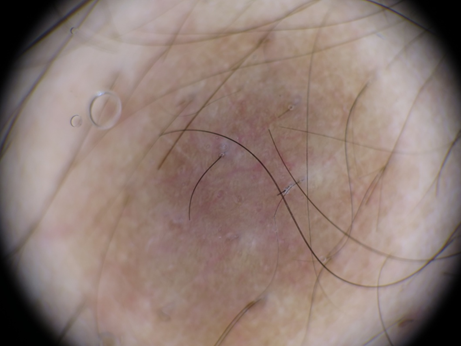

Figure 1&2 Case 1: 1 cm brownish nodule. dermatoscopy: delicate peripheral pigment network, central erythematous brownish amorphous area and branched pinkish vessels.

Figure 3&4 Case 2: 1.5cm brownish nodule. dermatoscopy: delicate peripheral pigment network, central wine red area and bright white areas.